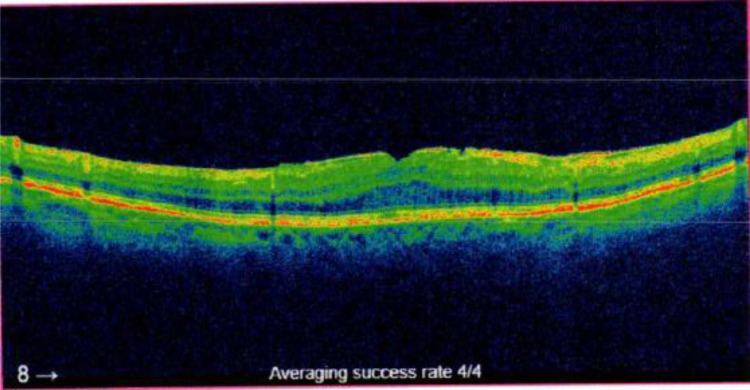

Patients and methods: A retrospective chart review was conducted on patients aged 18 and above diagnosed with postoperative or uveitic CME via optical coherence tomography from January 1, 2016, to December 31, 2023. Among these eligible patients, we investigated those treated with non-steroidal anti-inflammatory drugs (NSAIDs) and/or corticosteroids. The primary outcome was the duration until complete resolution of CME. Secondary outcomes included improvement of CME and the likelihood of CME recurrence after treatment. Statistical analysis involved ANOVA and Tukey's HSD test to compare treatment efficacy.

Abstract Image